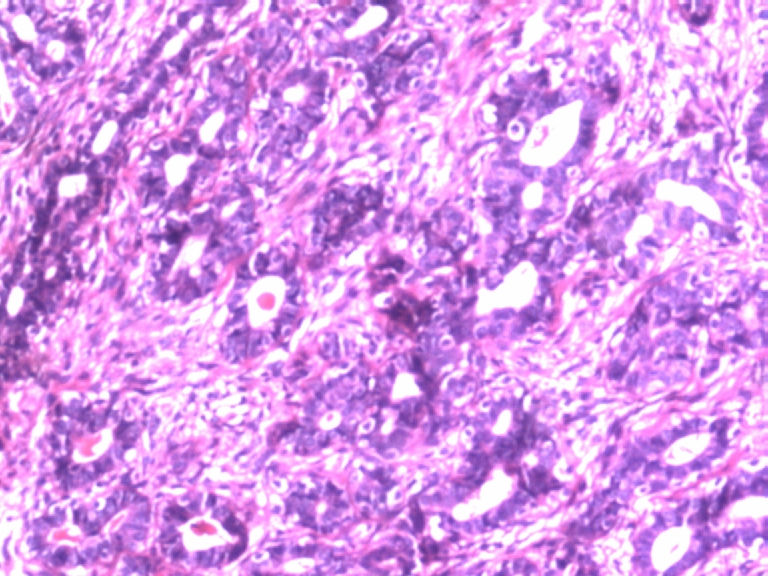

• 乳腺肿物图2

图2

患者,女,29岁,右侧乳腺肿物一个月。切面淡黄,均匀一致,质中。

标签:乳腺管状腺瘤

有肌上皮而且有的地方还有肌上皮增生,应该是腺病,你应该多采些低倍镜的图像,高倍镜的大多了没有太大的意义。

病变组织小叶结构未见,见管状、盲管状的腺管,周围似有空亮的肌上皮,腺上皮可见细小的核仁,染色质均细,导管上皮普通型增生。有包膜为盲管状腺瘤,则为腺病。